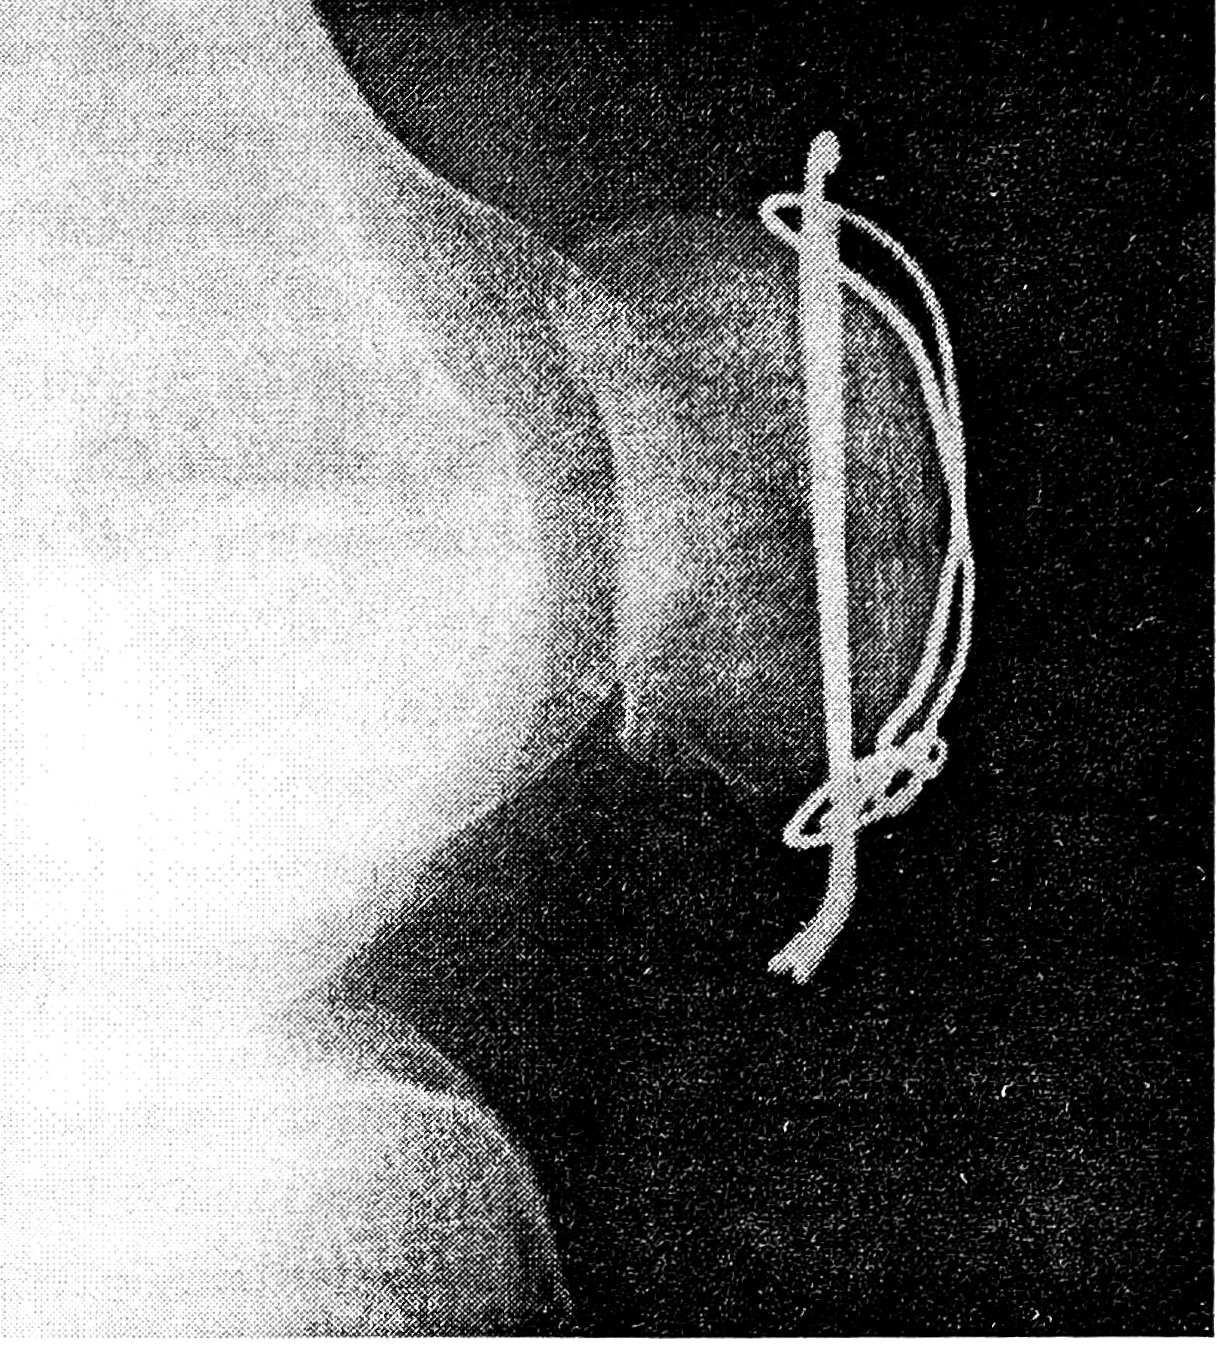

Техника операции. Все операции выполняются под жгутом. После чрескожной репозиции фрагментов и фиксации их винтовым зажимом сустав сгибают до угла 100—110°. Через нижнелатеральный доступ в полость сустава вводят артроскоп. Сустав отмывают от крови, после чего артроскопически контролируют качество репозиции при разогнутой конечности. Если смещение отломков сохраняется, делают попытку повторной репозиции. В ряде случаев, при сохраняющейся «ступеньке» на суставной поверхности надколенника, делают дополнительный разрез (с медиальной стороны надколенника) длиной 1—1,5 см, проходящий через поддерживающие надколенник связки. Через этот разрез в полость коленного сустава вводят щуп, с помощью которого, также под контролем артроскопа, производят устранение смещения костных фрагментов. При удовлетворительном расположении отломков над нижним и верхним полюсами надколенника делают два горизонтальных параллельных кожных разреза длиной 1—1,5 см. С помощью разработанного в клинике направителя через дистальный отломок в проксимальный проводят параллельно две спицы Киршнера. Винтовой зажим удаляют. Заряженную в ушко иглы проволоку проводят под дистально выстоящими концами спиц максимально близко к нижнему полюсу надколенника. Затем, используя специальные проводники, проводят ее субфасциально к проксимальным концам спиц, располагая на передней поверхности надколенника в виде «8» или О-образно. Проволоку натягивают и скручивают рядом с одним из проксимально выстоящих концов спиц. Сустав при этом находится в положении максимально возможного сгибания, исключающем «разрывное» воздействие на соединенные отломки. Излишки проволоки и спиц скусывают, скрутку погружают под проксимальные концы спиц в мягкие ткани. Проксимальные концы спиц загибают. Качество фиксации отломков проверяют сгибанием—разгибанием сустава, а также контролируют артроскопически. Артроскоп удаляют. На ранки накладывают шелковые швы (рис. 1).

Рис. 1. Схема расположения спиц и стягивающей проволочной петли.

К активным движениям в суставе больные приступали на следующий день после операции. В тот же день пациенты начинали ходить с дозированной нагрузкой оперированной конечности, пользуясь костылями. Для иммобилизации конечности мы использовали съемные шарнирные ортезы. Под контролем инструктора больные активно занимались лечебной гимнастикой, получали физиотерапевтические процедуры, массаж. Активное сгибание в суставе до угла 90° достигалось, как правило, на 3—4-й день после операции. В эти же сроки больных выписывали из стационара. Швы снимали в амбулаторных условиях на 10—12-й день после операции. Полную нагрузку на ногу без использования дополнительных средств опоры разрешали только при активном разгибании голени, что обычно достигалось к концу 2-й недели (рис. 2).

Рис. 2. Рентгенограмма больного после оперативного лечения.